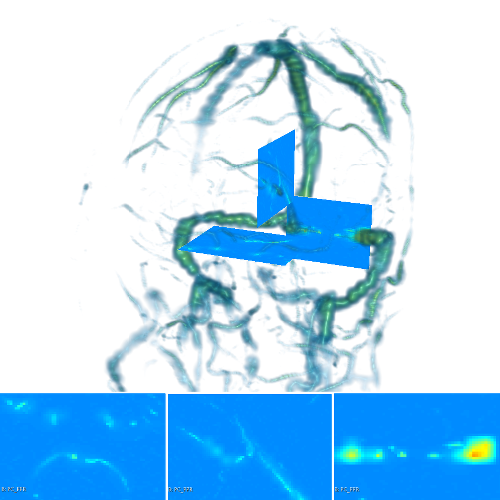

The scalar vesselness responses of both HCP and PC images are determined using the state-of-the-art Frangi filter (FFR) [8], and Optimally Oriented Flux (OOF) [12]. Also, the connected vesselness map (CVM) and the associated tensor field (TF) are synthesized for the same dataset using VTrails. The connectedness of the considered scalar maps is qualitatively assessed and the TF is inspected as proof of concept in section 3.1.

| Image | FFR | OOF | CVM | TF | |

| HCP |  |

|

|

|

|

| PC |  |

|

|

|

|

3.1 Connectedness of the Vesselness Map

Fig. 3 shows the connectedness of vessels recovered from state-of-the-art vascular enhancers and curvilinear ridge detectors FFR and OOF together with the proposed CVM for the synthetic HCP and the real PC images.

On the synthetic phantom, FFR shows a fragmented and rough vesselness response in correspondence of irregularly shaped sections of the structure. Also, the response at the bifurcation is not smoothly connected with the branches (triangular loop). Conversely, OOF recovers the phantom connectedness at the branch-point, and the vesselness response is consistent along the tortuous curvilinear section, however ghosting artifacts are observed as the shape of the phantom becomes irregular (C-like) or differs from a cylindrical tube. Also, close convoluted structures, which change scale rapidly in the HCP, produce inconsistent responses of OOF (fig. 3). CVM shows here a strongly connected vesselness response in correspondence of both regular and irregular tubular sections, with local maxima at structures’ mid-line. The connectedness of the structures is emphasized regardless the complexity of the shape, and it resolves spatially the tortuous curvilinear ‘kissing vessels’ without additional ghosting artifacts, despite the smooth profile.

Similar results are observed on the PC dataset: FFR has a poor connected response in the noisy and low-resolution image. Vessels are overall enhanced, however thin and fragmented structures remain disconnected. Overall, the vesselness response is not uniform within the noisy structures, where maximal values are often off-centred. A more consistent response is obtained from OOF, where the connectedness of vessels is improved. Maximal response is observed at the mid-line of vessels, however, noise rejection is poor. CVM strongly enhances here the vessel connectivity. The fragmented vessels of PC have a continuous and smooth response in CVM with higher values and a more defined profile. Large vessels shows solid connected regions with local maxima at mid-line as in OOF. Conversely from OOF, CVM shows improved noise rejection in the background.

The respective tensor fields (TF) synthesized on both HCP and PC show consistent features. The TF’s characteristics are in line with the connectedness of CVM: enhanced and connected vessels are associated with high anisotropy, whereas background areas show a predominant isotropic component.